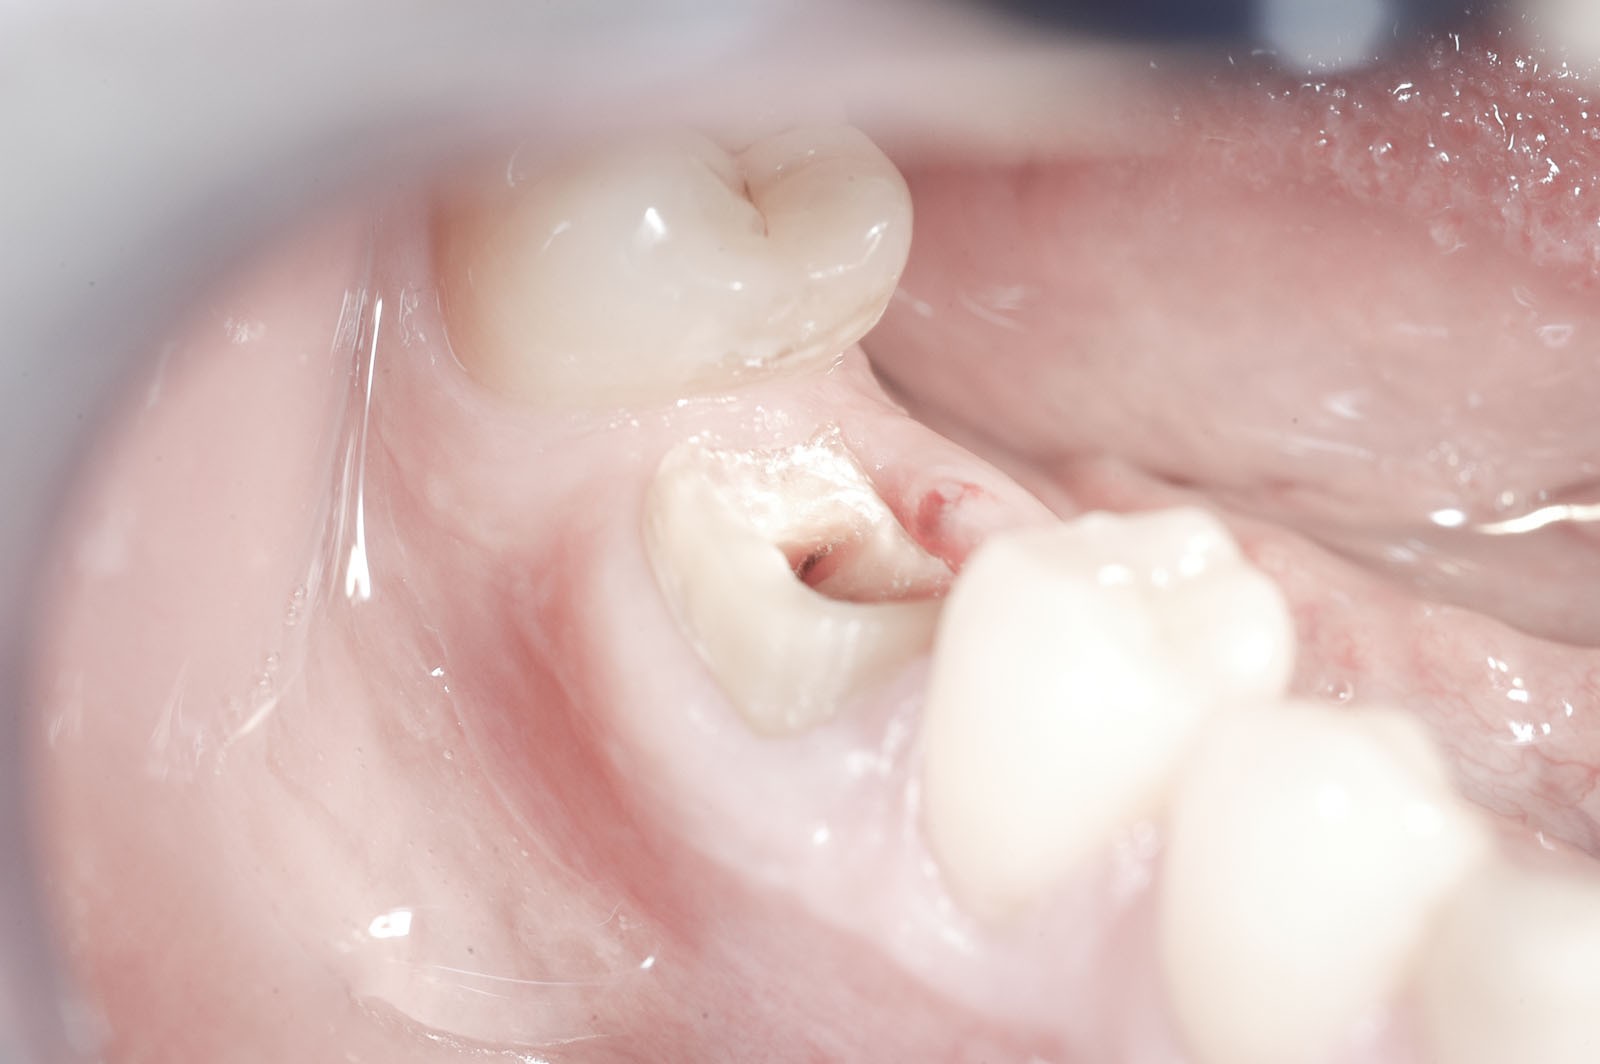

- Inlay Onlay Overlay – frezowane uzupełnienia stosowane w przypadku rozległych zniszczeń w strukturach twardych tkanek korony zęba w sytuacji, gdy typowa odbudowa materiałami kompozytowymi mogłaby okazać się nieskuteczna. Są wklejane specjalnymi cementami w wyprofilowany ubytek twardych tkanek korony zęba.

Wskazaniem do wykonania wkładów koronowo-korzeniowych jest wzmocnienie zęba leczonego kanałowo, w którym doszło do powstania dużego ubytku w jego części koronowej. Jeżeli ząb ma niewiele tkanek własnych lub są one uszkodzone, grozi to powstaniem naprężeń, w wyniku których może dojść do odłamania się jego ścian. Wkłady koronowo-korzeniowe zapobiegają uszkodzeniom mechanicznym zębów.

Inlay/Onlay, zwane nakładami koronowymi, to alternatywa dla wkładów, koron oraz wypełnień wykonanych metodą tradycyjną. Umożliwiają dokładną rekonstrukcję anatomicznego kształtu zęba, z pozostawieniem maksymalnej ilości tkanek własnych bez konieczności szlifowania. Są estetyczne, odporne na ścieranie, a przez to trwałe. Przygotowuje się je zwykle w laboratorium protetycznym na podstawie pobranego wycisku lub skanu, po uprzedniej preparacji zęba. Gotowe nakłady mocuje się w ubytkach cementami lub specjalnymi materiałami klejącymi, które cechuje duża adhezja. Wskazaniem do ich zastosowania są rozległe ubytki na powierzchniach zgryzowych, szczególnie istotne w zębach bocznych. Stosowane są również w celu precyzyjnej odbudowy powierzchni stycznych koron zębów, co jest istotne w celu zabezpieczenia brodawek dziąsłowych oraz poprawy higieny w przestrzeniach międzyzębowych.